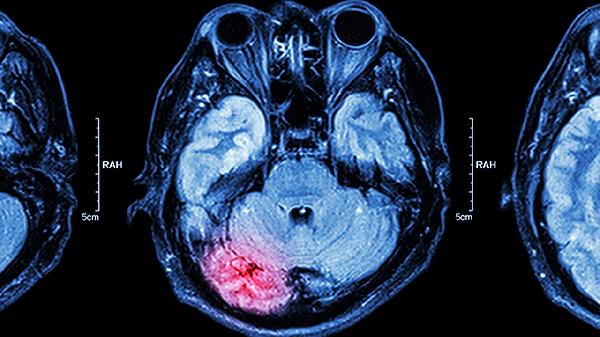

年轻人脑供血不足可能导致头痛、注意力下降、记忆力减退、眩晕等症状,严重时可引发短暂性脑缺血发作或脑梗死。主要后果包括认知功能受损、情绪障碍、肢体功能障碍、工作效率下降及生活质量降低。

运动皮层血流量降低时,可能出现单侧肢体麻木、持物不稳等局灶性症状。若椎基底动脉系统受累,可突发共济失调或吞咽困难。这类症状常提示存在动脉狭窄或微栓塞可能。

长期慢性缺氧会导致脑白质病变,患者可能出现持续性耳鸣、视物模糊等非特异性症状。夜间血氧饱和度下降还会加重晨起头痛,形成睡眠-觉醒节律障碍。动态血压监测有助于发现血管调节异常。